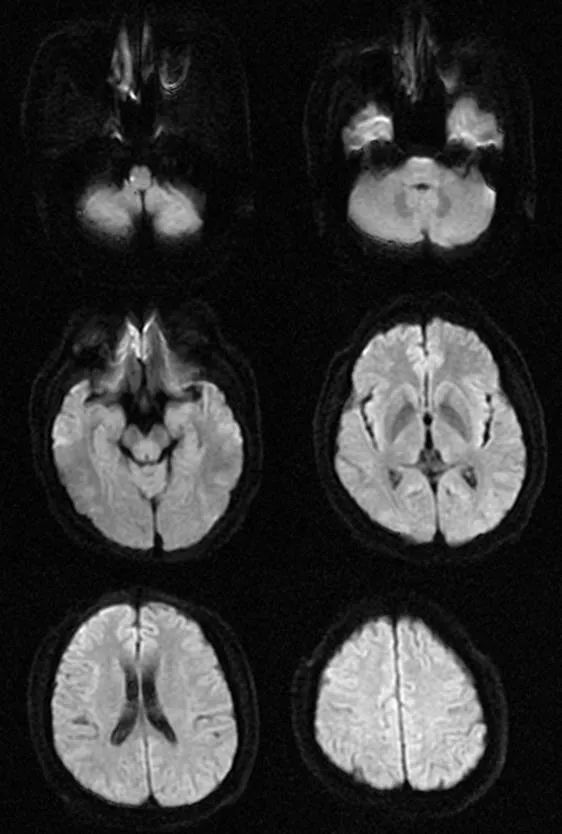

遗憾的是胸腰部 MRI 中 T1、T2、STIR 均未见明显异常,我们进一步完善头部 MRI,如下图:

从影像学可以看出 T2FLAIR、T1、T2 似乎也未见明显异常,此时该如何诊断,定位到底在哪里呢?

让我们再仔细看一下 DWI:

DWI 提示右侧延髓背外侧小点状高信号,弥散受限,提示急性脑梗死。